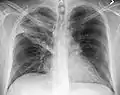

Normal AP CXR

AP CXR showing left lower lobe pneumonia associated with a small left sided pleural effusion